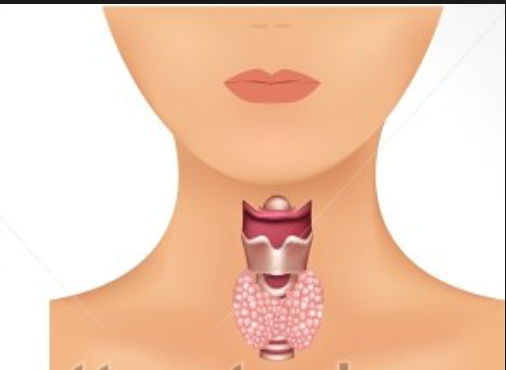

Thyroid Gland

Thyroid Gland